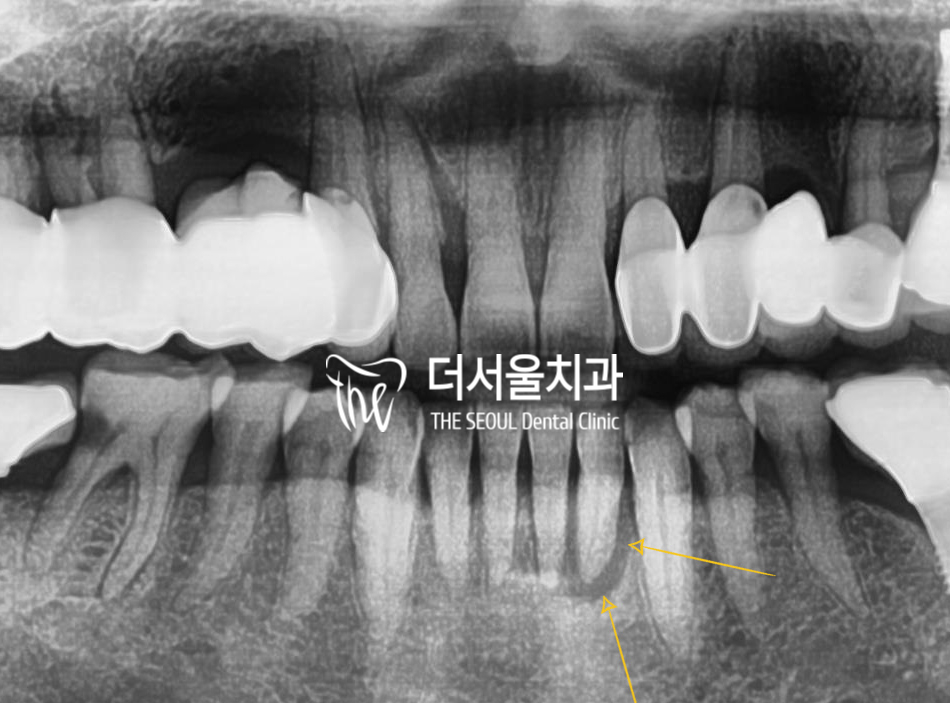

엑스레이를 보면 하악 앞니 뿌리 주위로

염증이 나타나 있는 것을 볼 수 있습니다.

영어로는 apical lesion 이라 부르는데

그 크기가 꽤나 큽니다.

여기서 해상도 높은 엑스레이를 찍어서 보면

골 소실의 범위도 조금 더 정확히 관찰을

할 수 있는데 치근단 염증이 위주로

넓게 퍼져나가 있는 것을 볼 수 있습니다.

이러니, 치아가 흔들릴 수 밖에 없겠죠.

더불어, 신경치료도 되어 있지 않아서

상당히 통증도 느끼고 있으셨던 상황이였습니다.